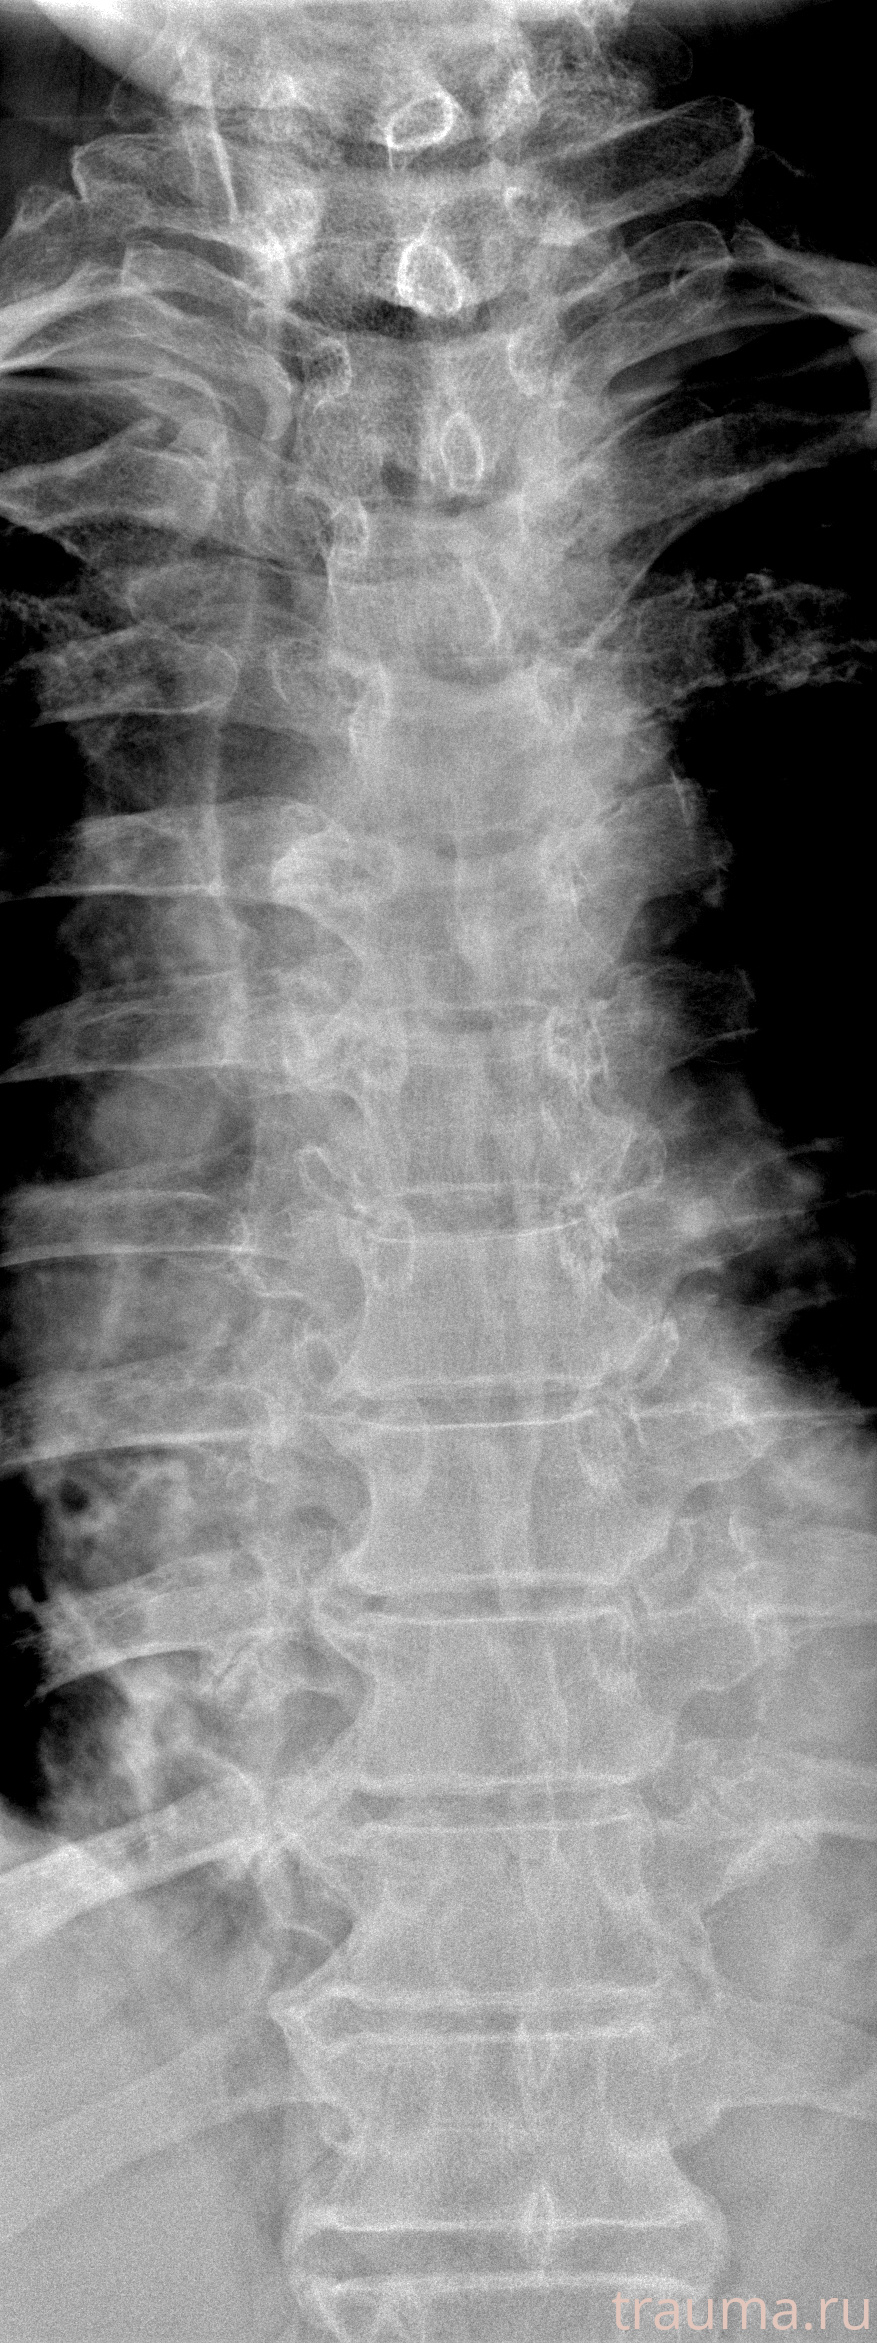

Рентгенограммы

Рентген на дому: по вашему адресу приезжает врач-рентгенолог, травматолог-ортопед с мобильным рентгеновским аппаратом, проводит диагностику травмы или заболевания, делает необходимые рентгенограммы, дает рекомендации по дальнейшему лечению. Получить качественные снимки в домашних условиях возможно благодаря уникальной методике, разработанной МосРентген Центром для института  Склифосовского